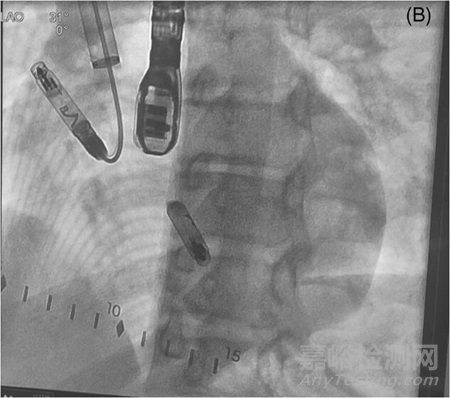

圖2 在需要部署的心房無(wú)導(dǎo)線展開(kāi)注角之前的左前斜肌